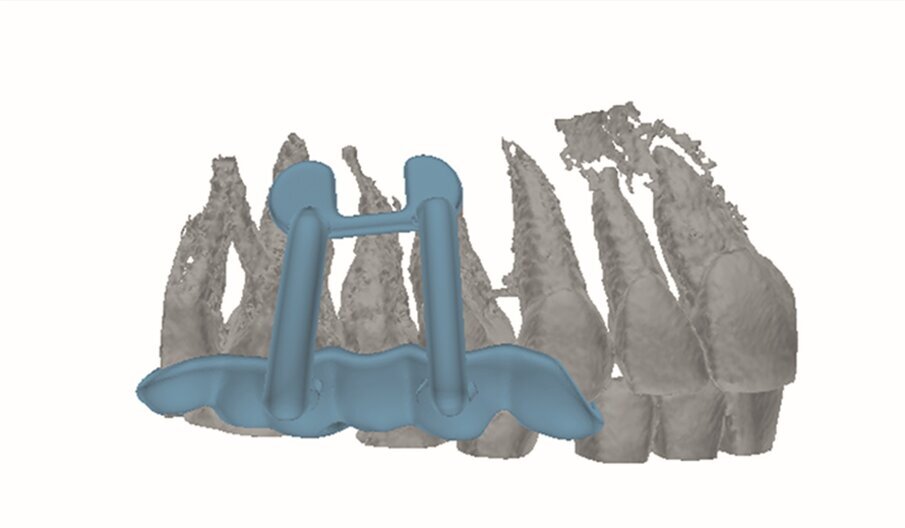

An intra-oral scan (TRIOS, 3Shape) of the mandible, and the resulting STL file was combined with the DICOM files of the CBCT scan to plan a surgical guide using the Blue Sky Bio software. A template that marked the limits of a cortical window to accurately reach the apical area was designed and printed (Fig. 1d).

An intra-oral scan (TRIOS) of the maxilla, and the resulting STL file (Fig. 2d) was combined with the DICOM files of the CBCT scan to plan a surgical guide using the Zirkonzahn. Implant-Planner software (Zirkonzahn) modified with Meshmixer (Autodesk). A template that marked the limits of a cortical window to accurately reach the apical area was designed and printed (Figs. 2e & f).

Fig. 2d: STL file obtained from the intra-oral scan.

Fig. 2e: Planned template for guided endodontic microsurgery of tooth #15.

Fig. 2f: Printed template for guided endodontic microsurgery of tooth #15.